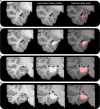

The hippocampus supports multiple cognitive functions including episodic memory. Recent work has highlighted functional differences along the anterior-posterior axis of the human hippocampus, but the neuroanatomical underpinnings of these differences remain unclear. We leveraged track-density imaging to systematically examine anatomical connectivity between the cortical mantle and the anterior-posterior axis of thein vivo human hippocampus. We first identified the most highly connected cortical areas and detailed the degree to which they preferentially connect along the anterior-posterior axis of the hippocampus. Then, using a tractography pipeline specifically tailored to measure the location and density of streamline endpoints within the hippocampus, we characterised where these cortical areas preferentially connect within the hippocampus. Our results provide new and detailed insights into how specific regions along the anterior-posterior axis of the hippocampus are associated with different cortical inputs/outputs and provide evidence that both gradients and circumscribed areas of dense extrinsic anatomical connectivity exist within the human hippocampus. These findings inform conceptual debates in the field and emphasise the importance of considering the hippocampus as a heterogeneous structure. Overall, our results represent a major advance in our ability to map the anatomical connectivity of the human hippocampusin vivo and inform our understanding of the neural architecture of hippocampal-dependent memory systems in the human brain.

The brain allows us to perceive and interact with our environment and to create and recall memories about our day-to-day lives. A sea-horse shaped structure in the brain, called the hippocampus, is critical for translating our perceptions into memories, and it does so in coordination with other brain regions. For example, different regions of the cerebral cortex (the outer layer of the brain) support different aspects of cognition, and pathways of information flow between the cerebral cortex and hippocampus underpin the healthy functioning of memory. Decades of research conducted into the brains of non-human primates show that specific regions of the cerebral cortex anatomically connect with different parts of the hippocampus to support this information flow. These insights form the foundation for existing theoretical models of how networks of neurons in the hippocampus and the cerebral cortex are connected. However, the human cerebral cortex has greatly expanded during our evolution, meaning that patterns of connectivity in the human brain may diverge from those in the brains of non-human primates. Deciphering human brain circuits in greater detail is crucial if we are to gain a better understanding of the structure and operation of the healthy human brain. However, obtaining comprehensive maps of anatomical connections between the hippocampus and cerebral cortex has been hampered by technical limitations. For example, magnetic resonance imaging (MRI), an approach that can be used to study the living human brain, suffers from insufficient image resolution. To overcome these issues, Dalton et al. used an imaging technique called diffusion weighted imaging which is used to study white matter pathways in the brain. They developed a tailored approach to create high-resolution maps showing how the hippocampus anatomically connects with the cerebral cortex in the healthy human brain. Dalton et al. produced detailed maps illustrating which areas of the cerebral cortex have high anatomical connectivity with the hippocampus and how different parts of the hippocampus preferentially connect to different neural circuits in the cortex. For example, the experiments demonstrate that highly connected areas in a cortical region called the temporal cortex connect to very specific, circumscribed regions within the hippocampus. These findings suggest that the hippocampus may consist of different neural circuits, each preferentially linked to defined areas of the cortex which are, in turn, associated with specific aspects of cognition. These observations further our knowledge of hippocampal-dependant memory circuits in the human brain and provide a foundation for the study of memory decline in aging and neurodegenerative diseases.